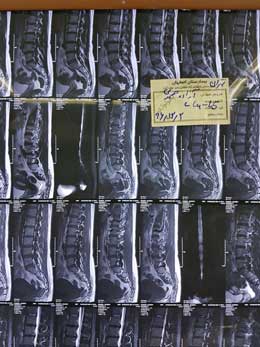

بیمار ۸۰۹ خانم آزاده صمدی از تهران مبتلا به هرنی دیسکال L4L5 از تهران

بیمار ۸۰۹ خانم آزاده صمدی از تهران مبتلا به هرنی دیسکال L4L5 از تهران در تاریخ96/12/2عمل شد.